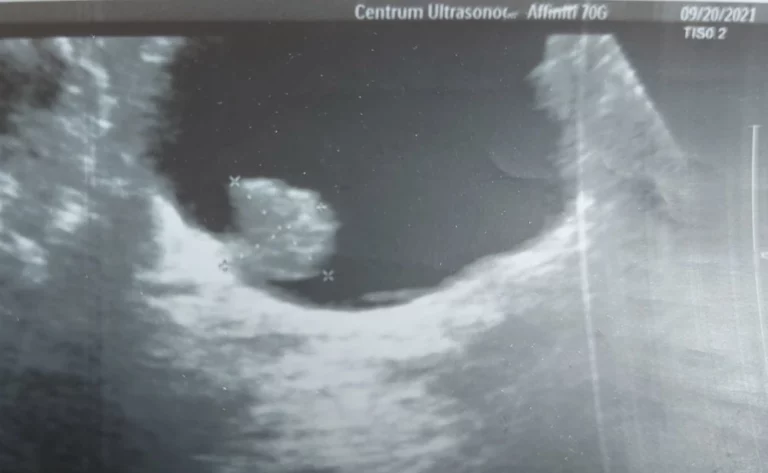

DEFINICJA: Nieprawidłowe ukształtowanie stawu, powstałe w okresie życia wewnątrzmacicznego, okresie okołoporodowym, jak również w pierwszych…